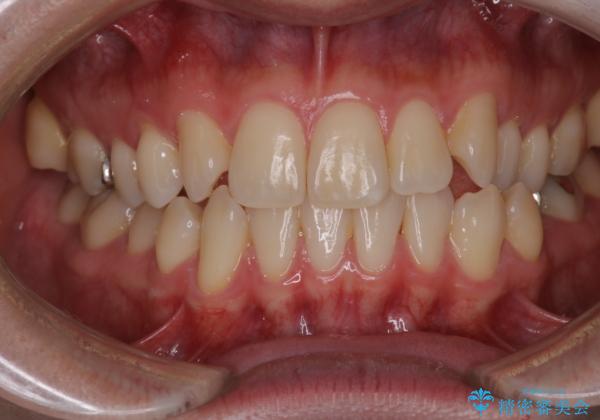

右上2番が欠損しているため、見た目と噛み合わせの両方のバランスを整えるために経過を追いながら必要な部位にゴム掛けをしました。

最終的に、見た目も噛み合わせも患者様に満足いただけました。

また矯正後、患者様の希望で

メタルインレーをセラミックインレーにやりかえさせていただき、さらに綺麗に仕上がりました。